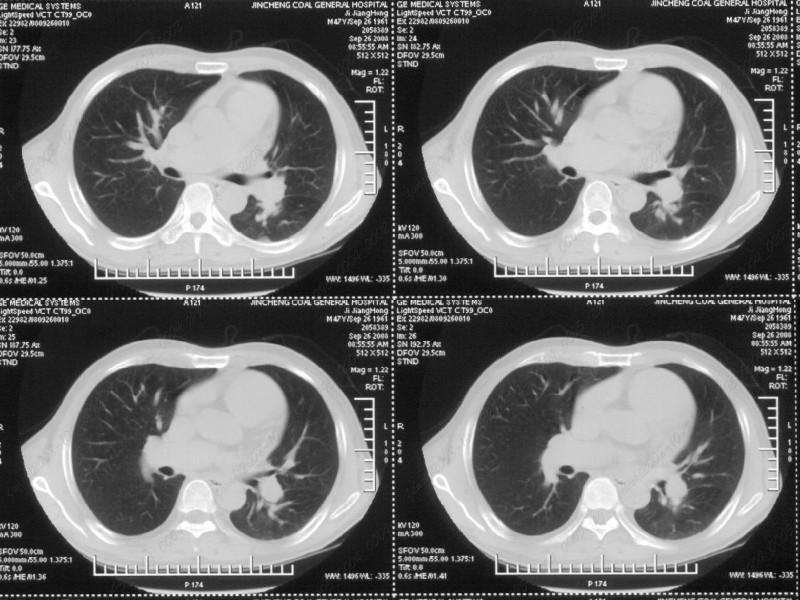

男性,47岁。胸部不适一年,ct检查发现右胸膜下结节。http://www.radida.com/bbs/forum.php?mod=viewthread&tid=46094

图像很清,资料很全。工作做的很细,向您学习!观阁下的强化图像发现,您们强化后扫描时间挺早,延迟时间大约在16—18秒之间吧。估计目的是为了观察肺动脉及分支的情况。但现有的资料并不能提示动脉栓塞改变。建议楼主可在机器上仔细观察,或许会有异常发现。另外,个人感觉右侧应为肺内结节而非胸膜结节。考虑肺内良性小结节,炎性假瘤可能性大。

病灶周围似有纤维化征像,增强明显强化,但中央可见点状低强化区,考虑慢性病变可能如炎性假瘤等,病灶边缘部分毛糙有切迹,双侧胸腔少量积液影,不除外恶性

结节未见明显强化,局部胸膜增后粘连,内缘纹理影增重伴小围星灶,局部胸膜下小三角状实变影,尖端见纤维索牵扯征,综合考虑炎性病变,有增殖表现,不出外tb灶

汇报临床诊断:右肺动脉分枝栓塞

右肺静脉充盈缺损,左心房体积小,右肺动脉远端动脉充盈缺损,右肺血管影细小,考虑;右肺动脉远端栓塞.